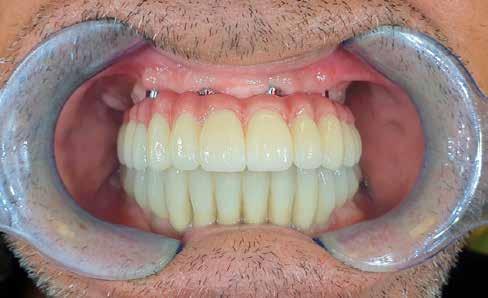

TELJES SZÁJRESTAURÁCIÓ

A-TÓL Z-IG

A megbízható márkákra való támaszkodás számos előnnyel jár a labor zökkenőmentes működése tekintetében. Ez azt jelenti, hogy ismerni kell a termékeket és meg kell tapasztalni az értéküket a tényleges munka során. A legnagyobb kihívás a teljes száj rehabilitációja és az elvesztett funkciók helyreállítása, a komfort biztosítása, miközben természetes esztétikai megjelenést biztosítunk, amely minden betegtípusnál (alak, méret, életkor stb.) személyre szabott.